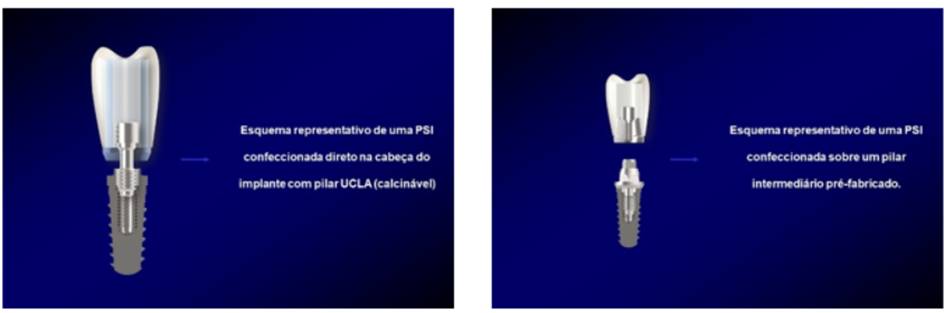

Outro fato que merece ser destacado é a forma de confecção das próteses sobre implantes, se direto na cabeça do implante ou se usando um pilar intermediário e parafusando ou cimentando a PSI sobre o pilar. Dessa forma, a primeira diferença entre o pilar UCLA e os demais pilares se refere à forma de confecção da PSI, uma direto sobre a cabeça do implante utilizando-se do pilar UCLA (assemelhando-se a um “pivot” cuja coroa está integrada ao núcleo-pino em um único sistema pela ausência de espaço interoclusal), e a outra forma em que o profissional fará uso do pilar e sobre este teremos uma prótese que será cimentada ou parafusada, vide imagens da Figura 2 (Zavanelli et al., 2003; Zavanelli et al., 2011).

Essa forma de confecção da PSI, direto na cabeça do implante com pilar UCLA ou sobre um pilar, tem suas indicações. No entanto, passa também pela escolha e preferência dos profissionais. Vale ressaltar a versatilidade desse componente UCLA, podendo ser utilizado em casos unitários ou múltiplos, cimentados ou parafusados e em implantes de conexão HE (Hexágono Externo), HI (Hexágono Interno) ou CM (Cone Morse).